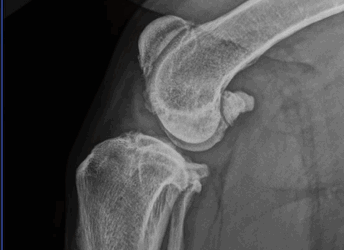

Medial Patellar Luxation

Medial patellar luxation (MPL) is a dislocation of the kneecap (patella) toward the inside aspect of the leg.